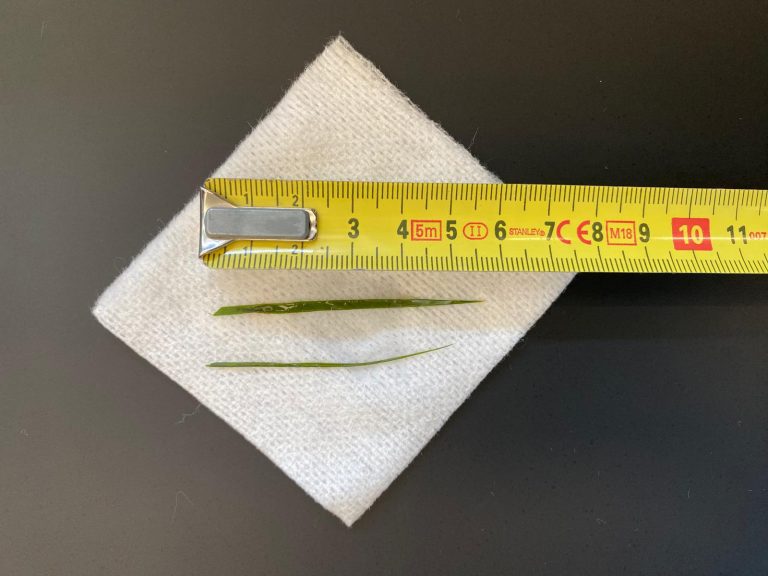

Tijdens de operatie doet Olaf het erg goed. Zijn hartslag en ademhaling blijven netjes stabiel. Bij exploratie van de wond in het gehemelte, blijkt dit een scheur tot in het bot te zijn, van ongeveer 3 cm. We kunnen zo de neusholte inkijken, wat het bloed uit de neus verklaart. Uit het gehemelte zijn 3 kogelfragmentjes en enkele losse botfragmentjes verwijderd waarna de wond gehecht is. De wond op de tong is een lange scheur over de lengterichting, die geen fragmentjes bevat. Achter in de bek is een klein gaatje zichtbaar in het zachte gehemelte, waarachter ook een gaatje in het slijmvlies van de keel zichtbaar is. Meest waarschijnlijk is dit het traject dat de kogel heeft afgelegd, tot in de nek. Helaas kunnen we het fragmentje dat achter in het keelslijmvlies aanwezig is niet bereiken. Op de neus is een wondje zichtbaar, waar op de röntgenfoto ook een fragmentje in aanwezig is. Gelukkig kunnen we deze gemakkelijk verwijderen en de huid sluiten met knoophechtinkjes. Als laatste is het kogeltje uit de nek verwijderd. Deze lag ingebed tussen de spierlagen, maar had geen grote schade aangericht op deze plek.